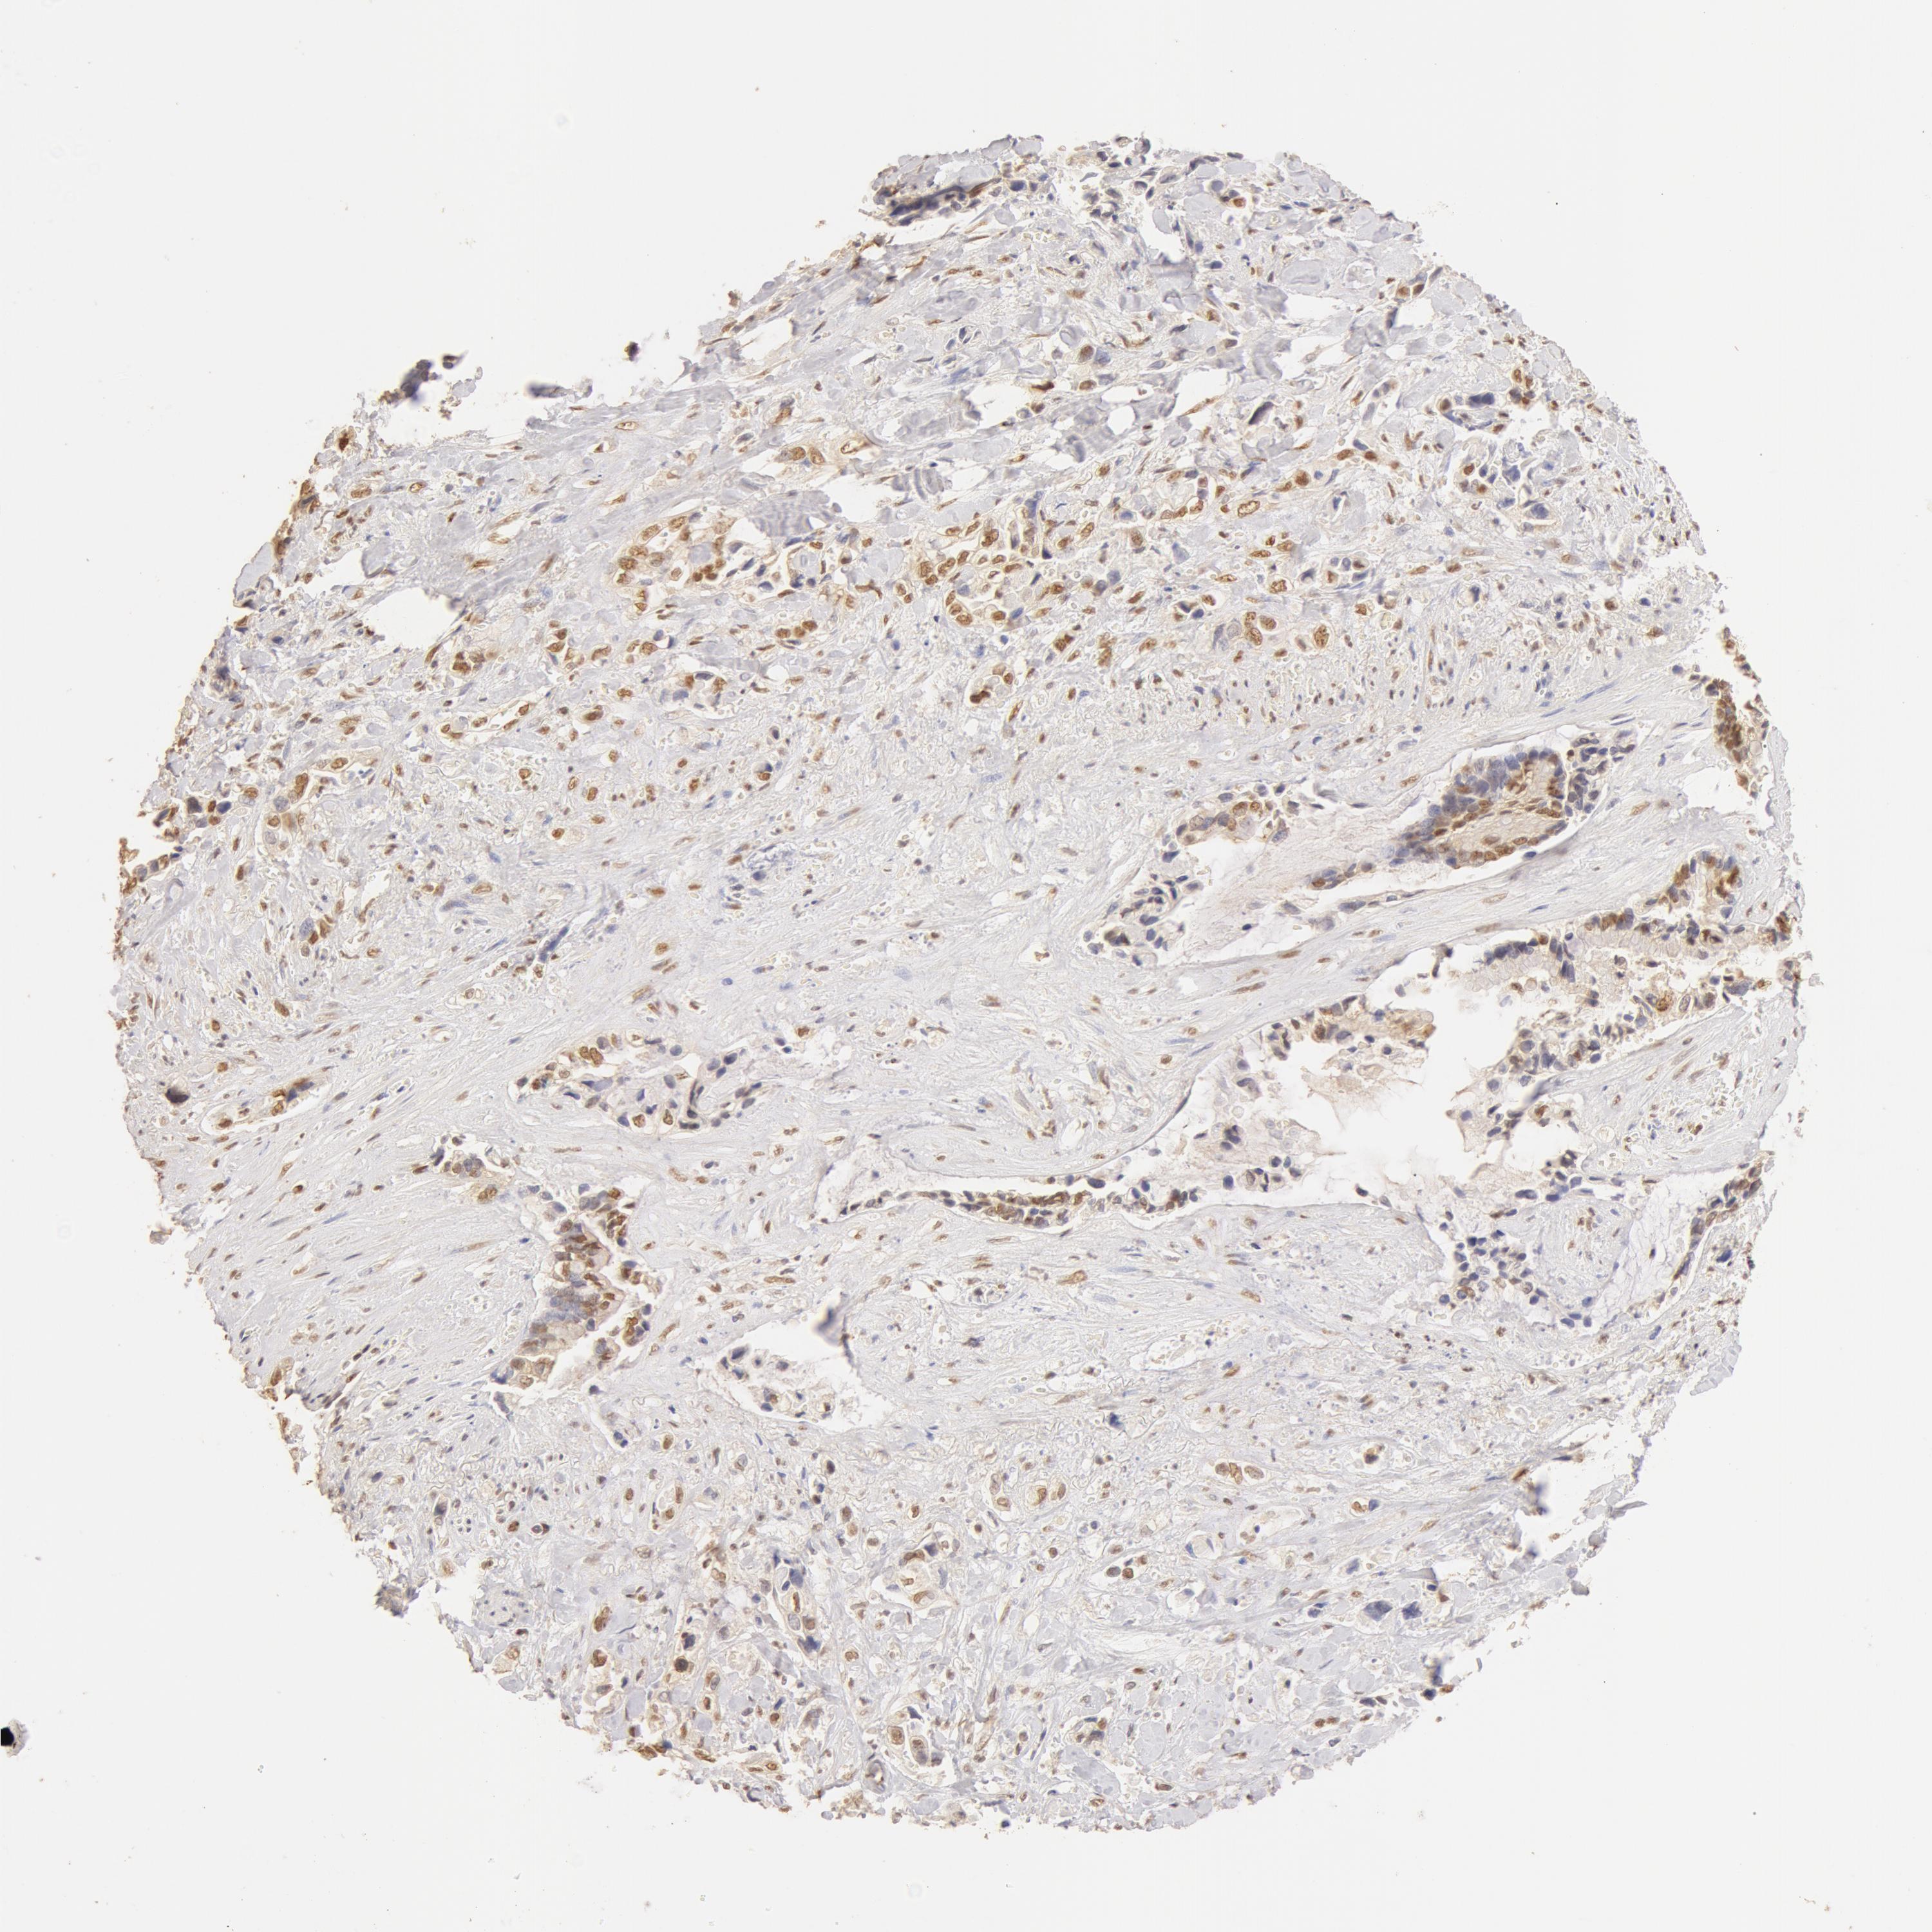

PANCREATIC CANCER - Protein expressioni

A mouse-over function shows sample information and annotation data. Click on an image to view it in a full screen mode. Samples can be filtered based on level of antibody staining by selecting one or several of the following categories: high, medium, low and not detected. The assay and annotation is described here.

Note that samples used for immunohistochemistry by the Human Protein Atlas do not correspond to samples in the TCGA dataset.

Antibody stainingi

Antibody staining in the annotated cell types in the current human tissue is reported as not detected, low, medium, or high, based on conventional immunohistochemistry profiling in selected tissues. This score is based on the combination of the staining intensity and fraction of stained cells.

Each image is clickable and will lead to virtual microscopy that enables deeper exploration of all samples and also displays staining intensity scores, fraction scores and subcellular localization as well as patient and tissue information for each sample.

Antibody HPA042050

Antibody HPA043516

Antibody CAB001718

Staining

High

Medium

Low

Not detected

Intensity

Strong

Moderate

Weak

Negative

Quantity

>75%

75%-25%

<25%

None

Location

Nuclear

Cytoplasmic/membranous

Cytoplasmic/membranous,nuclear

Adenocarcinoma, NOS